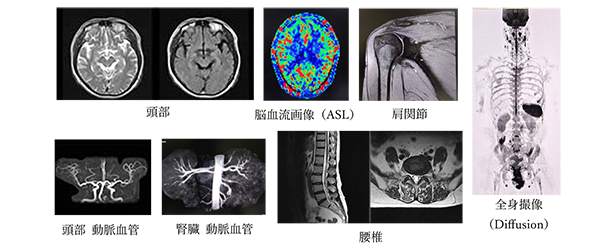

MRI検査

MRI検査とは?

強力な磁石と電磁波を使って、身体の内部を撮像をする検査です。

最大の特徴は、CT検査と異なり放射線を使用しないことです。そのため、被ばくの心配がなく、脳、脊髄、血管、お腹、手足など、全身を安心して詳しく検査することができます。

当院では、令和7年4月より最新のAI技術と画像処理技術を搭載した新型装置「MAGNETOM AItea1.5T」を導入いたしました。従来よりも更に質の高い画像が得られるようになり、より正確な診断と適切な治療方針決定の手助けができるようになりました。